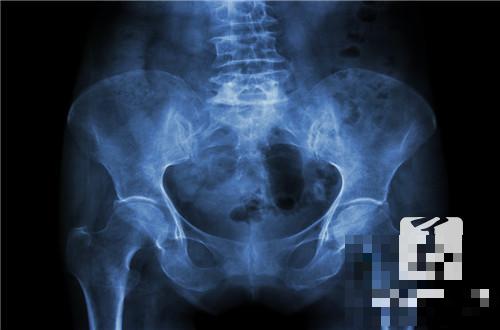

盆腔积液是一种比较常见的健康问题,如果盆腔积液超过了10mm的话,就属于病理性的盆腔积液了。这种盆腔积液对于女性的健康危害比较大,在发病的时候,也会给女性带来各种痛苦,比如说肚子疼的厉害,就很有可能是因为病理性的盆腔积液所导致的。下面,就为大家介绍一下盆腔积液的治疗方法!

盆腔积液就是盆腔存在炎性渗出物,可发生在子宫内膜发炎后,内膜组织肿胀的细胞中渗出的略黏稠的液体,被周围组织包裹所渐渐形成的囊性包块。如果不加以治疗的话,可以慢慢长大。中药外治法可使药效直达病灶,得以快速发挥疗效,迅速改善患处生理功能,修复炎症组织。御雪清治疗盆腔炎、盆腔积液以其安全无副作用,故治疗盆腔炎症中医是最佳选择。除了女性因生理特点有正常的盆腔积液外,病理性的盆腔积液多是盆腔炎或子宫内膜异位症。盆腔积液可发生在盆腔炎、附件炎或子宫内膜异位症之后。按病理因素可分为生理性盆腔积液和病理性盆腔积液两种。生理性盆腔积液对女性来说并非是一件坏事情,病理性盆腔积液危害较大,一旦女性发现异常盆腔积液,应及时到医院就诊,对症治疗。